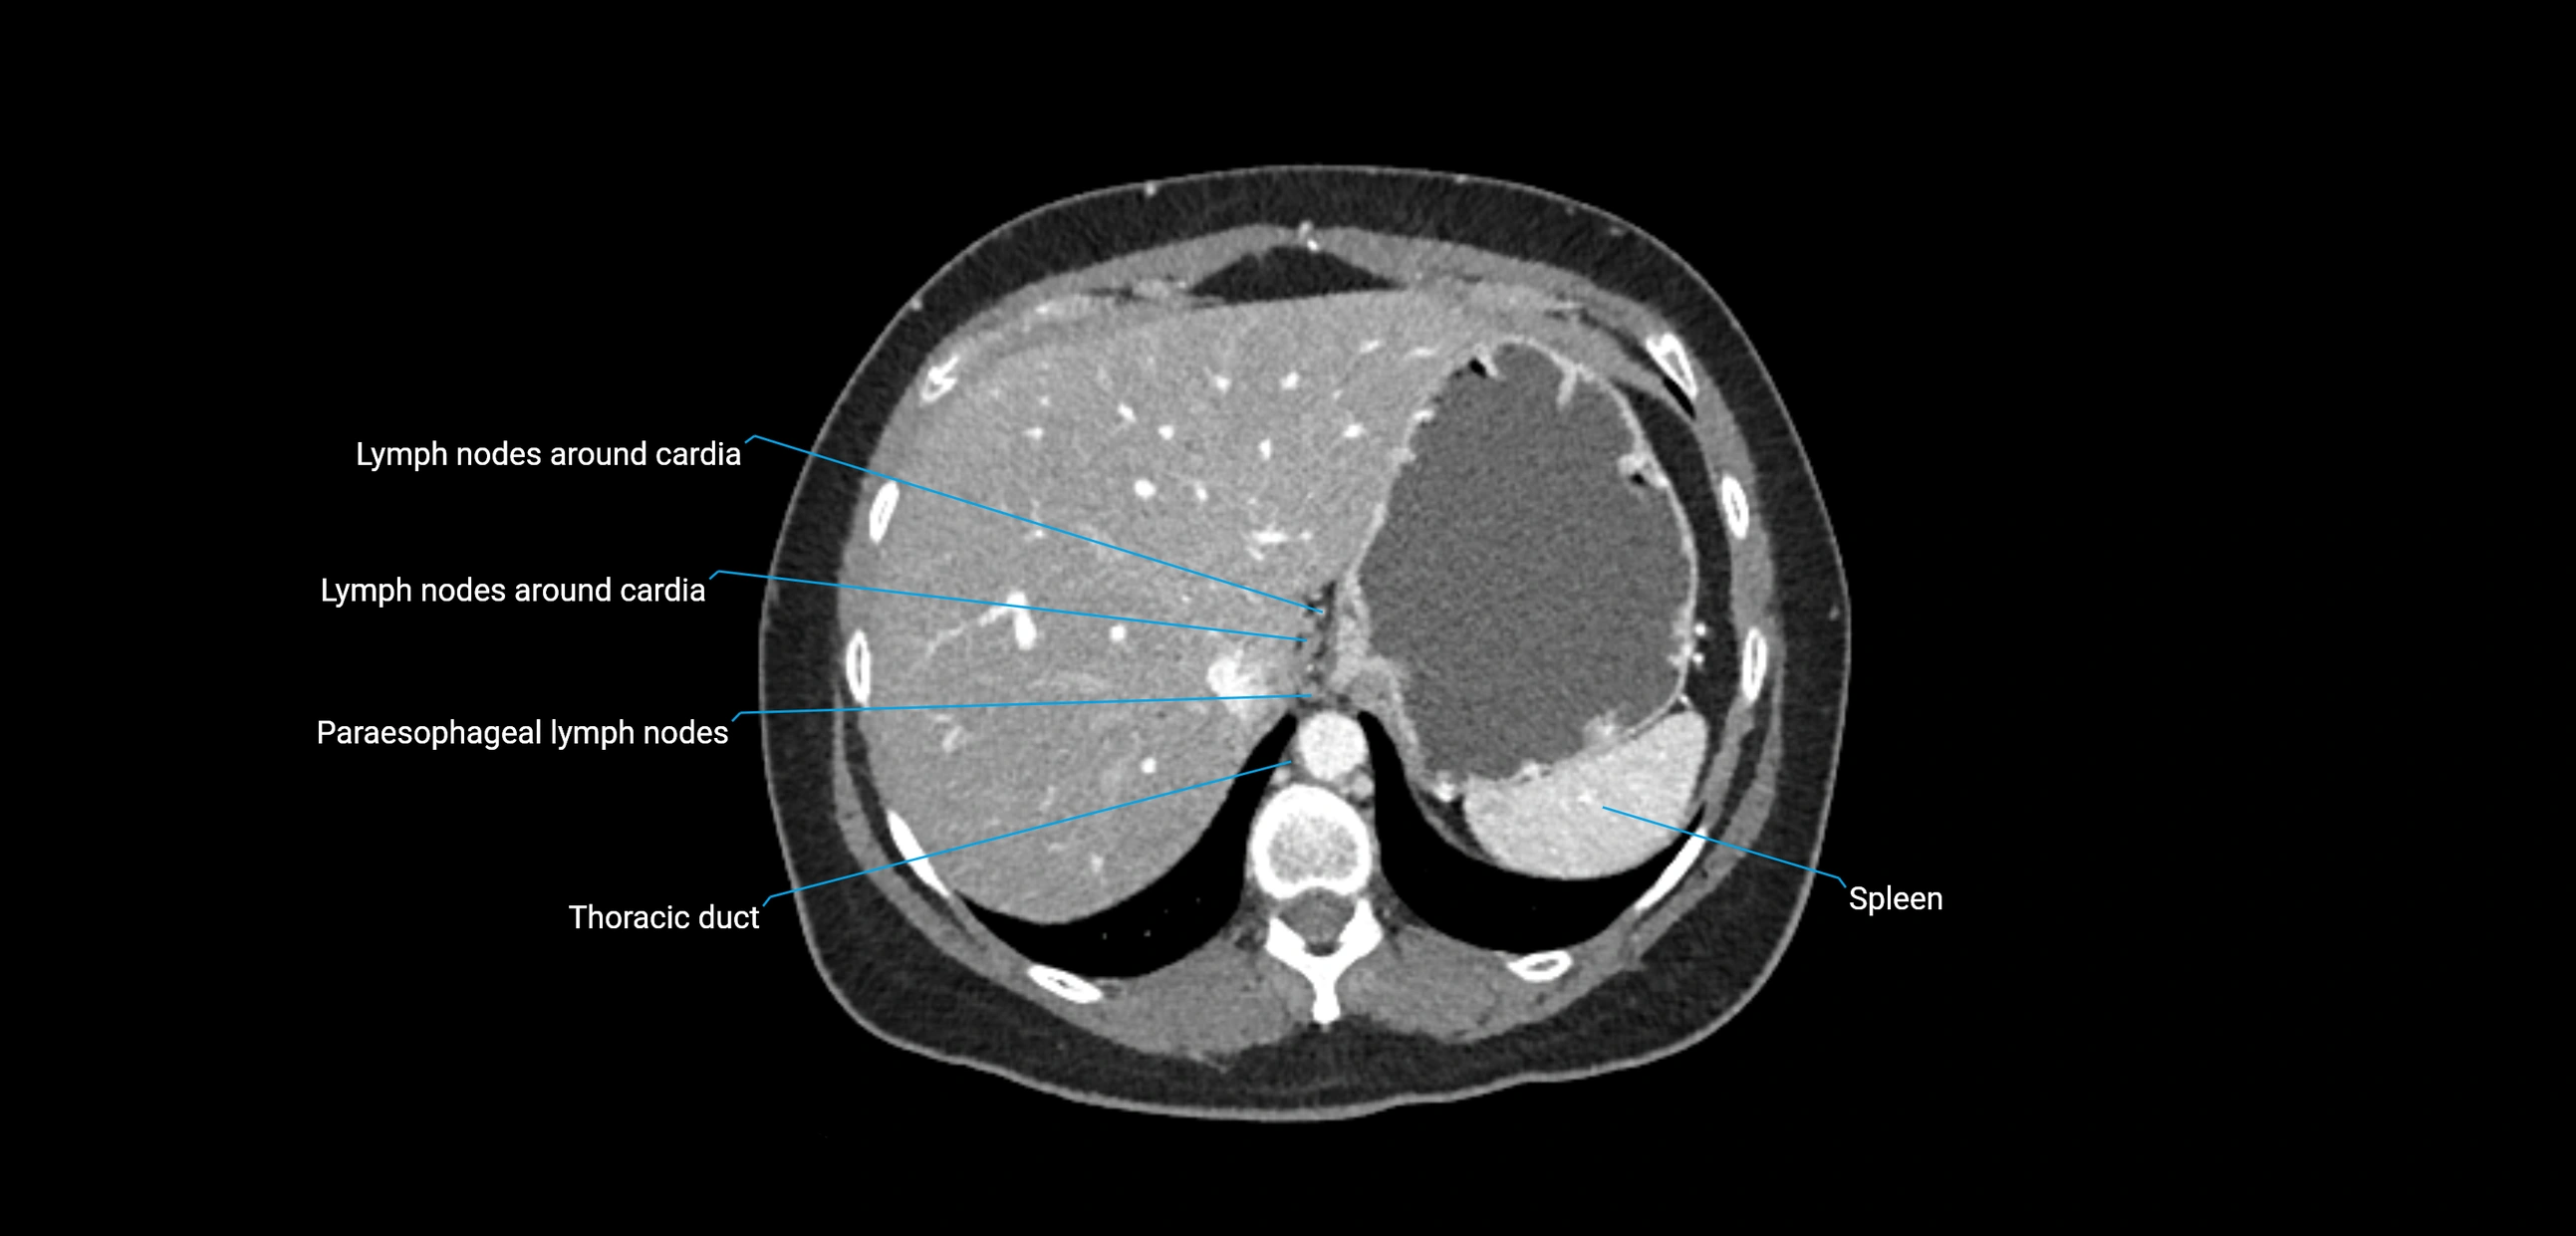

CT Appearance

CT Pre-Contrast:

• Nodes appear as soft-tissue density nodules adjacent to the aorta and IVC

• Calcification may be seen in chronic infections (e.g., tuberculosis)

CT Post-Contrast:

• Normal nodes enhance homogeneously

• Malignant nodes may show heterogeneous enhancement, central necrosis, or conglomerate formation

• Size >1 cm short axis is suspicious, though morphology and distribution are equally important